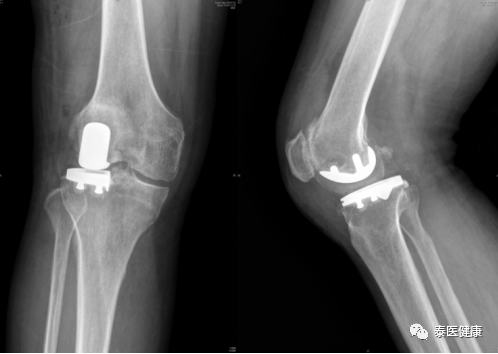

术前

术后

手术保留了内侧半月板及前后交叉韧带,保留了膝关节大部分的骨质,不切股四头肌,不翻髌骨,不干扰伸膝结构,减少了对股四头肌的损伤。患者术后第二天开始下地活动,现已康复出院,恢复良好。